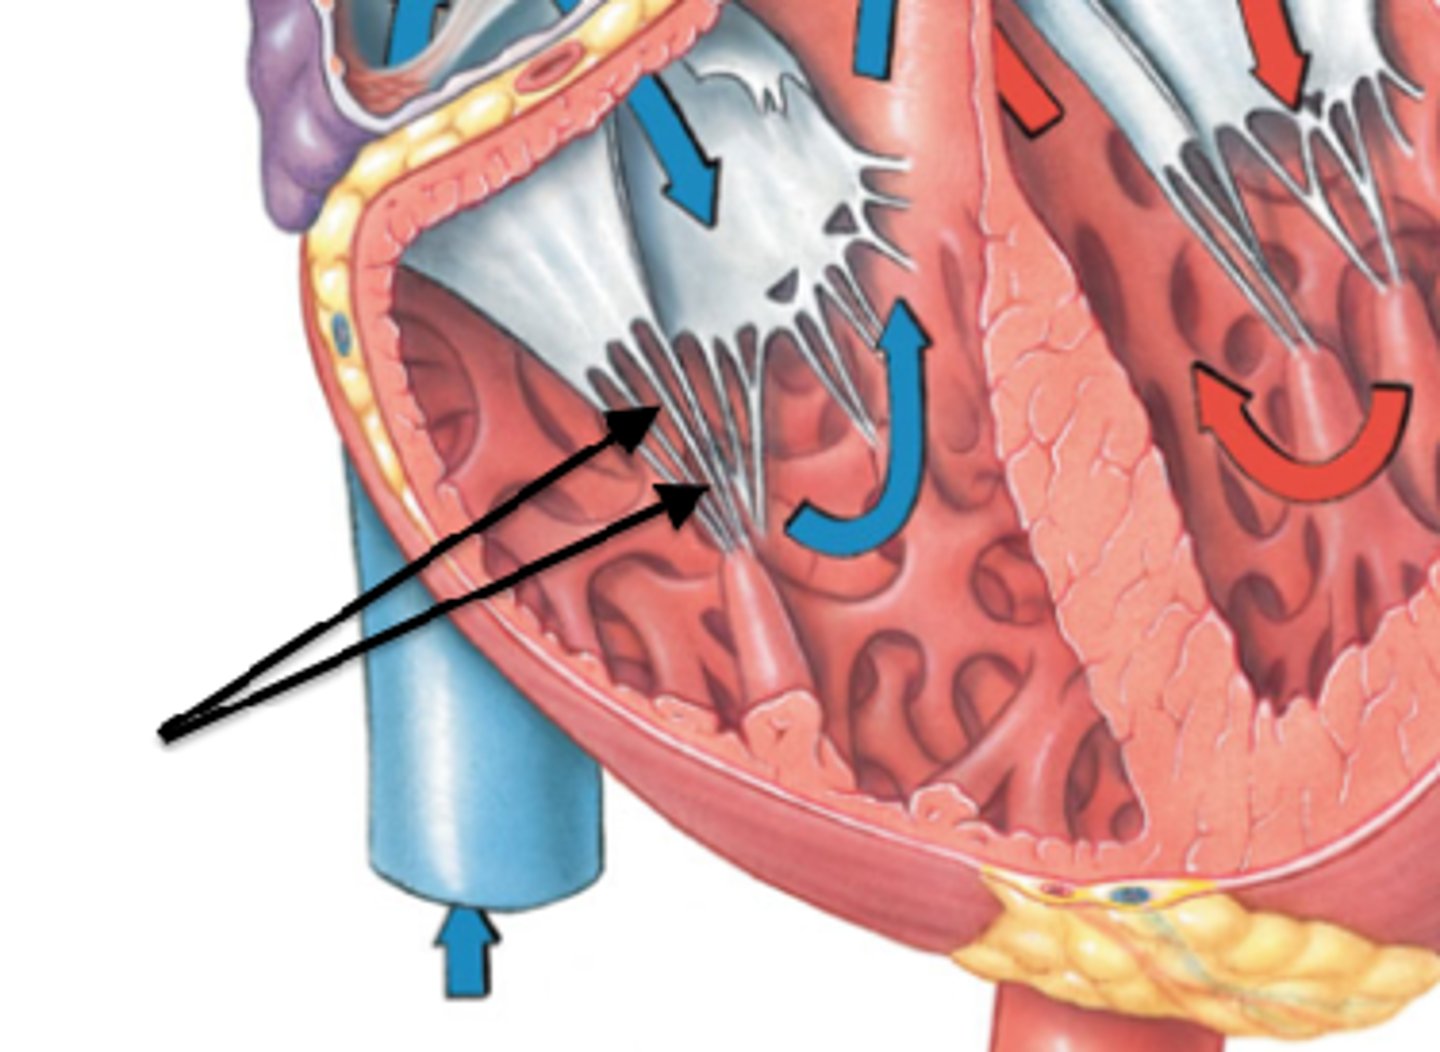

Tricuspid valve

structure. DH

Papillary muscles (3)

structure. on both sides. DH.

Tendinous cords

feature. Strings on top of the papillary muscle. DH.

Trabeculae carneae muscle

Structure. Beef jerky, meat.